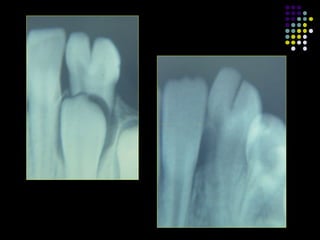

Geminacion:

 Etiologia desconocida.

 Formacion incompleta de dos dientes.

 Intento de hacer dos dientes de un unico organo del

esmalte.

 Hendidura parcial: dos coronas compartiendo el

mismo canal radicular.

 Ocasionalmente: hendidura completa (generalizada)

dos dientes de un mismo germen.

 Causa de apiñamiento.

Fusion:

 Union de dos germenes dentarios en

desarrollo.

 Resultado: estructura dentaria unica/grande.

 Involucra: todo el diente/raices.

 Canales radiculares: separados/compartidos.

 Imposible diferenciar fusion de dientes

supernumerarios normales de Geminacion.

 Mayor afeccion de incisivos.